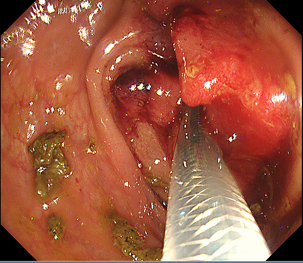

消化管の狭くなっている部分に対してステント(筒のようなもの)を挿入し狭窄部を広げる治療になります。

主に癌などの悪性腫瘍の狭窄に対して行う治療で、切除不能狭窄の症状緩和目的や腸閉塞症状を伴う狭窄の緊急手術回避目的で行います。